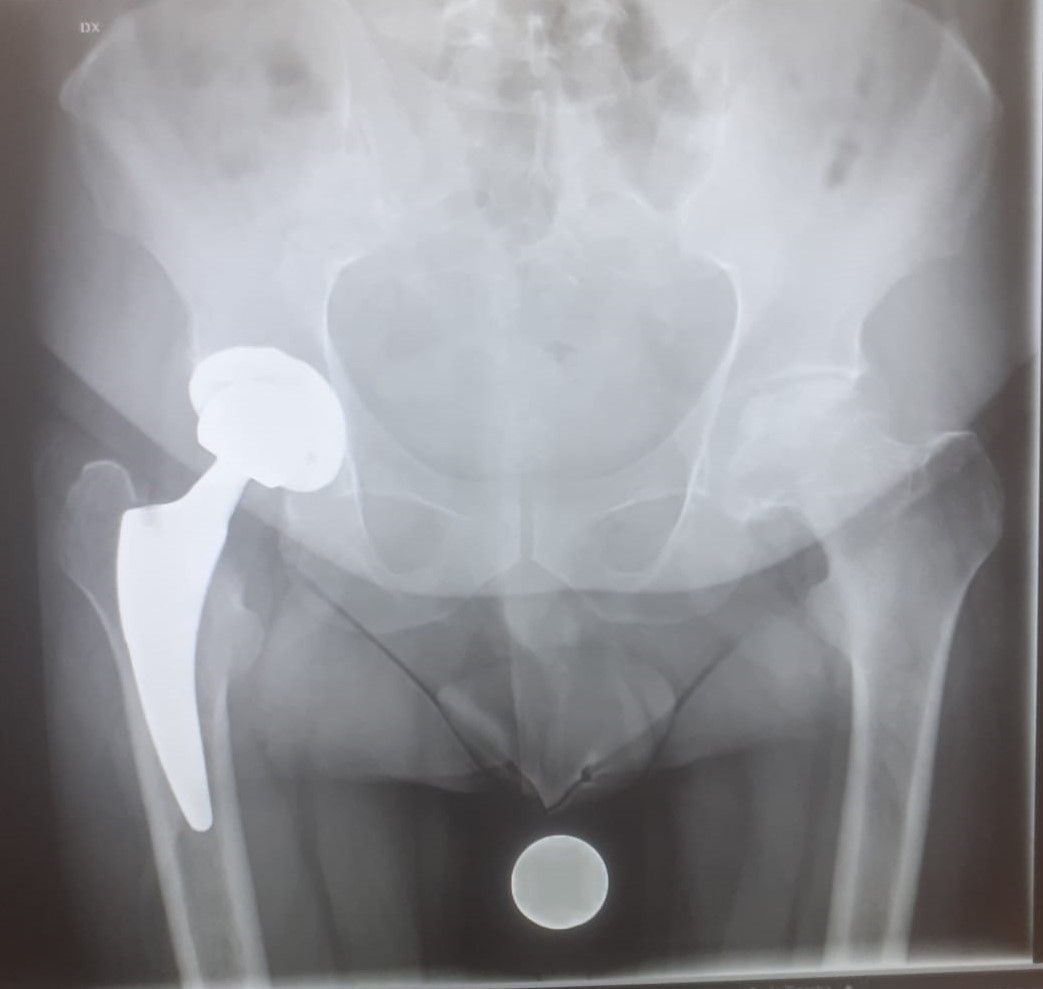

L’operazione viene effettuata attraverso un’incisione praticata all’altezza dell’anca. La testa del femore viene rimossa e la cavità viene preparata ad accogliere una superficie artificiale detta protesi. La testa e il collo del femore sono sostituiti con una protesi di metallo di alta qualità, mentre la cavità viene sostituita con un guscio di metallo rivestito da plastica chirurgica ad alta densità.

A seconda del tipo, può essere necessario cementare la protesi all’osso: alcuni tipi di protesi, invece, non devono essere cementati, perché l’osso circostante cresce all’interno della protesi e la cementa autonomamente. Alla fine dell’operazione la pelle viene ricucita e per, rimuovere l’eventuale liquido in eccesso, può essere usato un drenaggio.

- Con la prima tecnica, quella più diffusa, il femore viene sostituito completamente.